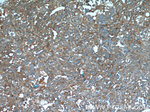

IGFBP7 Antibody in Immunohistochemistry (Paraffin) (IHC (P))

图: 1 / 12

IGFBP7 Antibody (19961-1-AP) in IHC (P)

Immunohistochemistry of paraffin-embedded human liver cancer tissue slide using 19961-1-AP ( IGFBP7 Antibody) at dilution of 1:50 (under 40x lens). {{ $ctrl.currentElement.advancedVerification.fullName }} 验证信息 View more